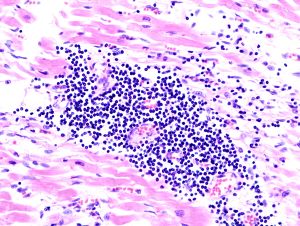

| صورة نسيجية لالتهاب فيروسي لعضلة القلب في عملية تشريح لمريض مصاب بالمرض. | |

يتم كشف التهاب العضلة القلبية عن طريق استخدام مخطط القلب الكهربائي(ECG)،وهناك أيضاً علامات للالتهاب من عدم انتظام تركيز الكرياتين (creatine)، والتروبونين (troponin). ويمكن كشفها أيضاً عن طريق عمل القسطرة، بحيث يتم عمل فحص لنسيج القلب، بحيث يتم أخذ عينة صغيرة من النسيج الداخلي والخارجي للقلب، ويتم فحصها من قبل مختص أمراض من خلال مجهر ضوئي. حديثاً، أصبح بالإمكان الكشف من خلال استخدام جهاز الأشعة المغناطيسية لمنطقة القلب (cMRI: Cardiac Magnetic Resonance Image)، وقد تبين أنها طريقة نافعة.